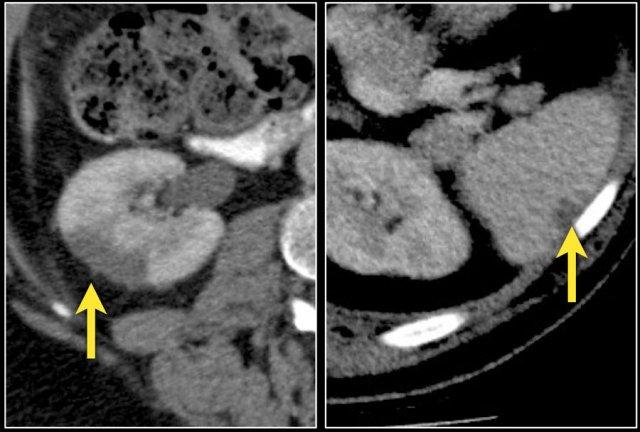

Đặc điểm điển hình của ung thư biểu mô tế bào sáng là ngấm thuốc mạnh trong thì vỏ-tủy (corticomedullary phase).

Điều này có thể khó đánh giá khi tổn thương nhỏ và nằm ở vỏ thận, vốn cũng ngấm thuốc mạnh.

Do đó, thì thận (nephrogenic phase) là thì nhạy cảm nhất để phát hiện các tổn thương này, vì nhu mô thận ngấm thuốc đồng nhất và đậm hơn so với khối u (hình minh họa).

Tổn thương thâm nhiễm ở cực trên thận phải, hầu như không thấy trên ảnh không tiêm thuốc (bên trái), thấy rõ ràng ở thì thận (bên phải). Giải phẫu bệnh xác nhận RCC tế bào sáng